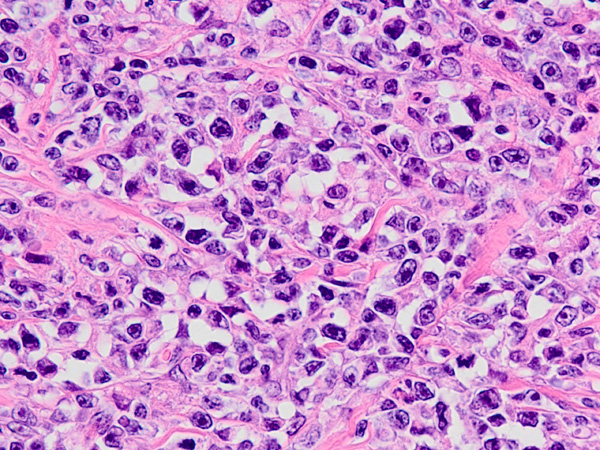

猫ちゃんが嘔吐と食欲不振の症状で来院されました。超音波画像から腫瘍による腸閉塞が疑われたため、開腹手術を行いました。病理組織検査の結果は「リンパ腫(高グレード、貫壁性)」でした。その後、抗がん剤による治療となりました。